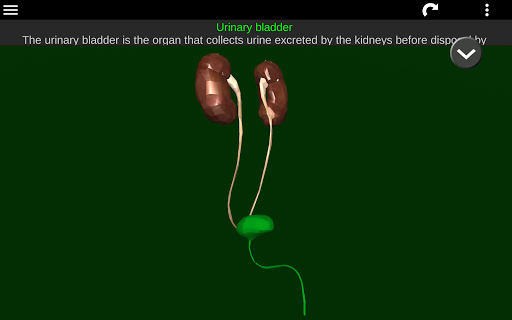

* Sistem pencernaan, termasuk lambung, usus kecil, usus besar, dan animasi sistem ini.